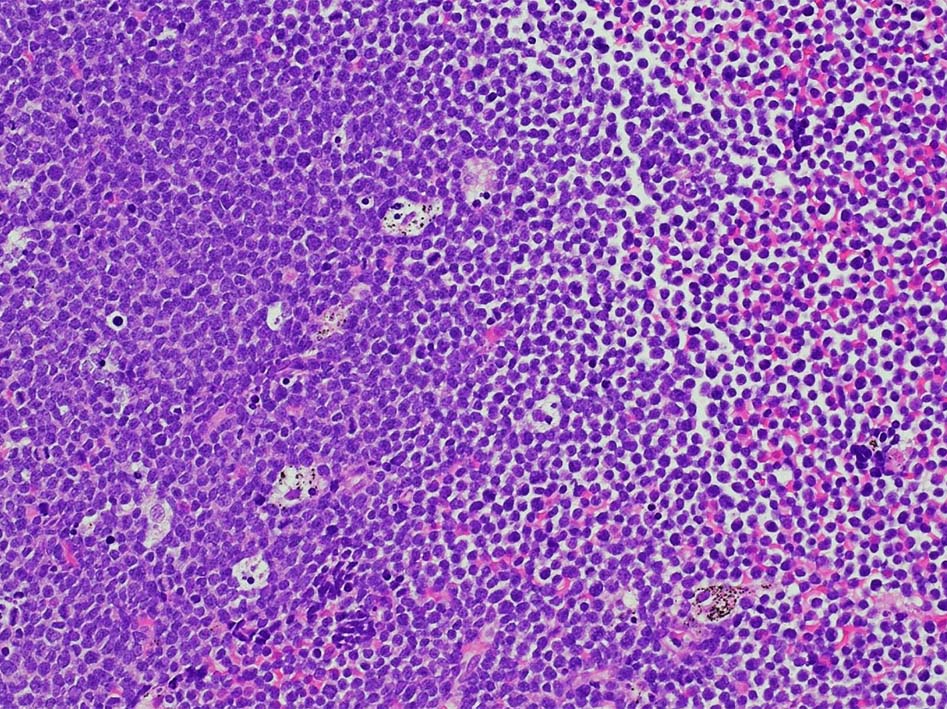

右肺上葉から前縦隔に90mm大の腫瘤あり. 右胸水貯留を伴う. 右主気管支より縦隔腫瘍のEBUS-TBNAをおこなう.

断片状組織片が採取され, 小型から中型の円形細胞がシート状密に増殖する. tindible body macrophagesが散在しstarry-sky様組織像を呈する組織片がある. CD3+, CD5+, CD20-, Ki-67 LI veru high(>95%),CD10-, BCL2(淡染だがほぼ100%膜陽性), BCL6陽性, MYC+(69%). T-cell neoplasmであるが, double expressorである. EBER-ISH陰性. CD4, CD8 double positive cellの増殖. CD25-, TIA1, granzymeBはいずれも陰性.